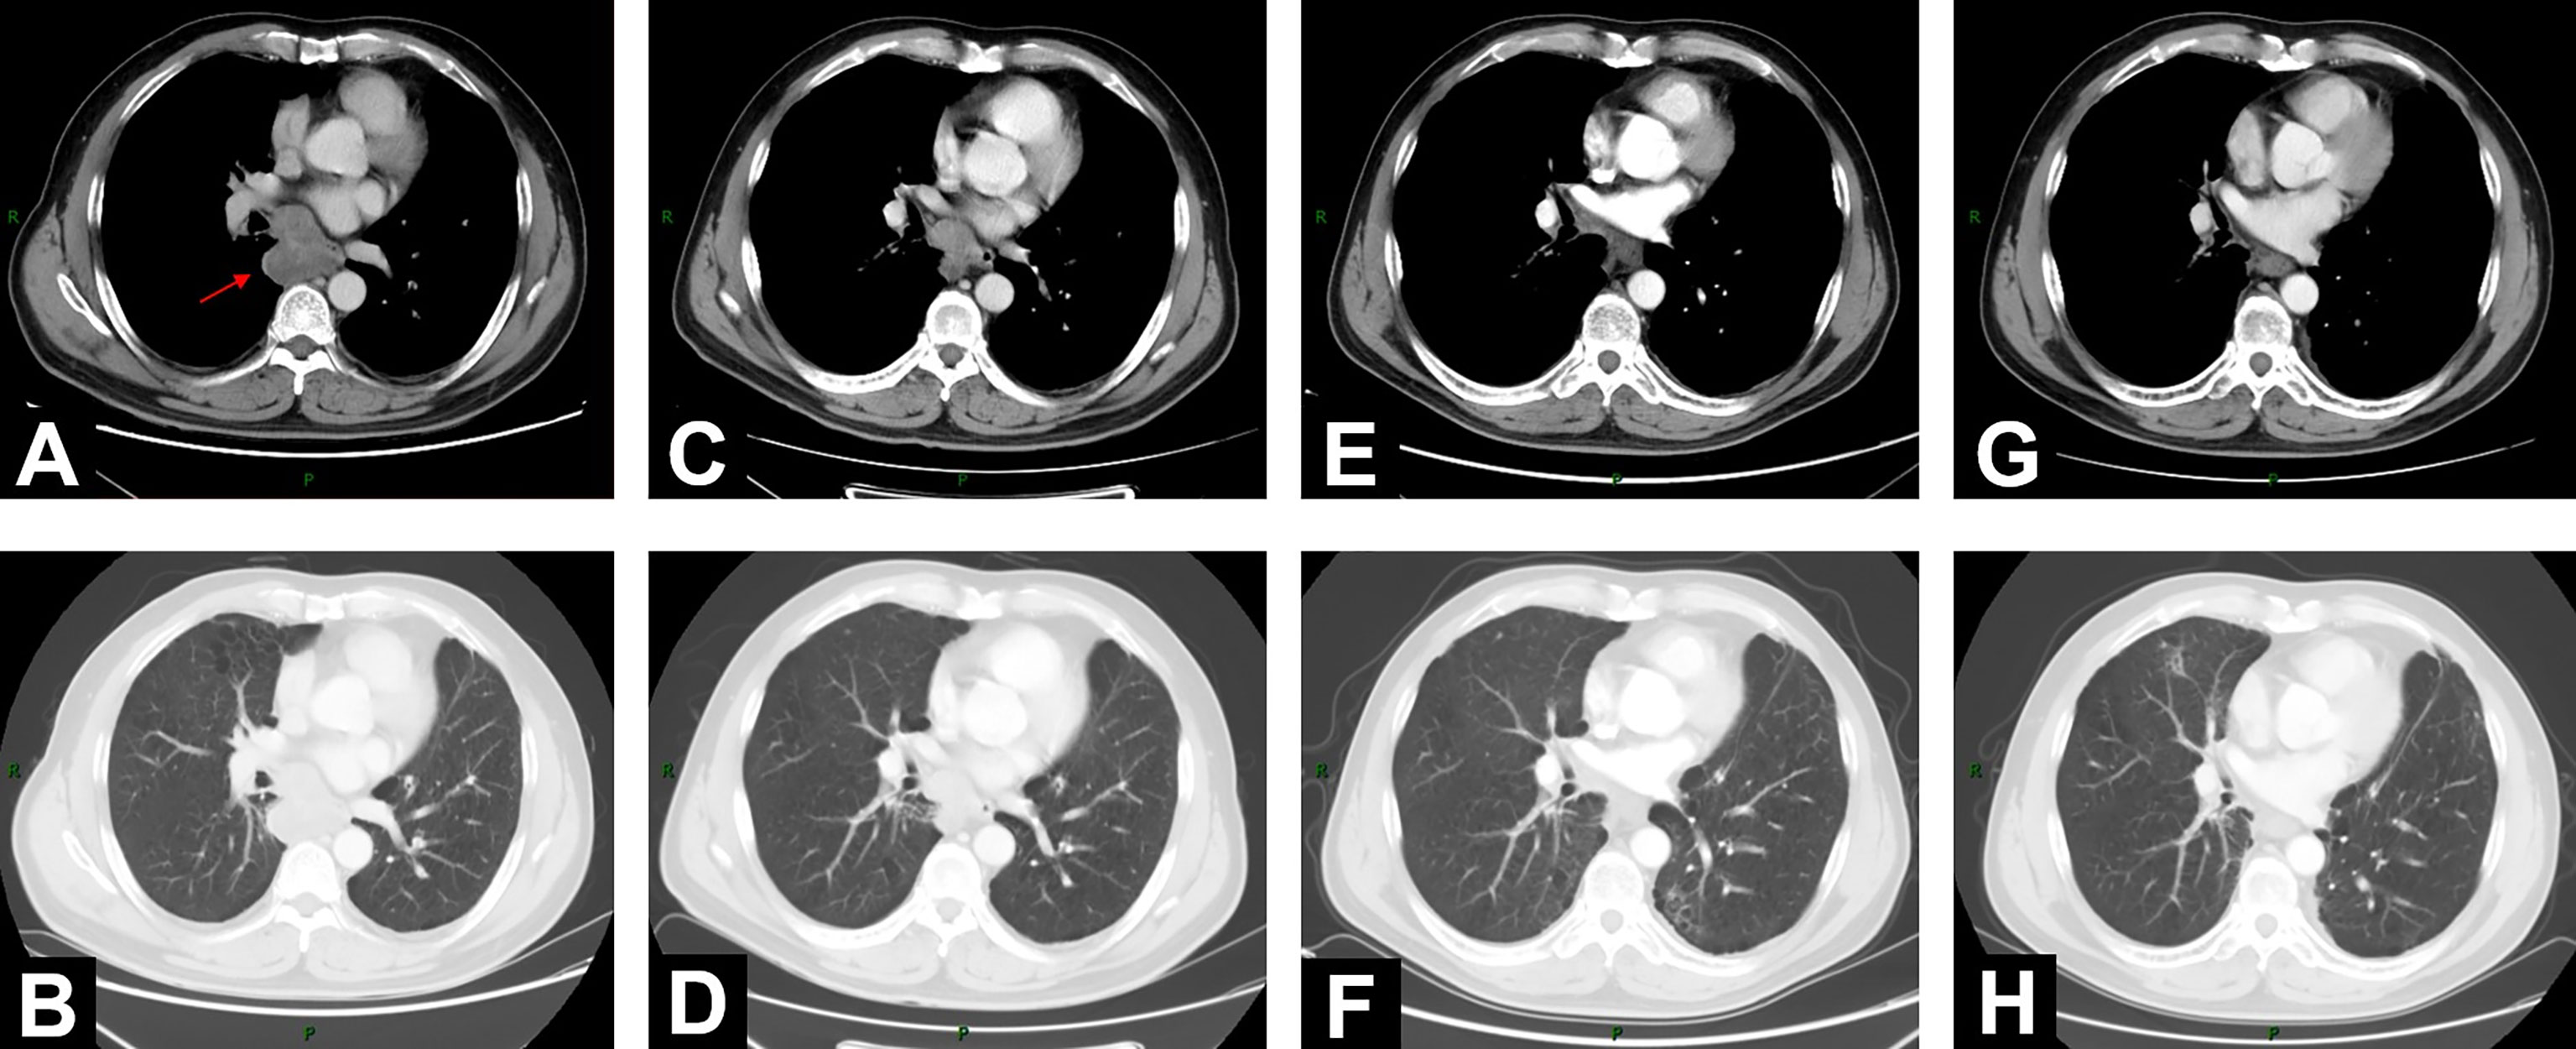

On June 18, 2020, 2 years after the left lung bullae resection, CT scan demonstrated an irregularly enlarged mediastinal lymph node station 7 with heterogeneous enhancement, about 5.2 cm * 4.7 cm, considered as the metastasis, but no visible primary pulmonary parenchymal focus (Figures 1A, B). Subsequent bronchoscopy did not reveal any primary lung lesion either. Positron emission tomography (PET)/CT suggested the enlarged mediastinal lymph node station 7 with increased 18F-fluorodeoxyglucose (18F-FDG) uptake and unclear boundary with adjacent esophagus. The corresponding maximum standardized uptake value (SUV) of the enlargement was 22.2, and it was considered a metastasis possibly from a pulmonary origin, while no obvious pulmonary lesion with positive 18F-FDG uptake was found (Figure 2A). Hence, unexpectedly, the primary lesion remained unclear even after PET/CT. No evidence of distant metastasis emerged after performing PET/CT, brain MRI, and whole-body radioactive bone scan (Figure 2B). Physical examination (PE) also was negative.

Figure 1 Changes of mediastinal lesion on chest contrast-enhanced CT scans. (A, B) On June 18, 2020, CT demonstrated enlarged mediastinal lymph node station 7 with heterogeneous enhancement (5.2 cm * 4.7 cm). (C, D) CT on August 11, 2020, after 2-cycle induction chemotherapy (3.9 cm * 2.9 cm). (E, F) CT on November 13, 2020 (2.0 cm * 1.5 cm), 1 month after concurrent chemoradiotherapy (cCRT). (G, H) At 1-year follow-up after consolidation durvalumab, CT on October 26, 2021 (1.6 cm * 1.3 cm).

On August 11, 2020, after 2 cycles of induction chemotherapy (paclitaxel liposome 300 mg d1 + nedaplatin 140 mg d1/q21d), the patient was well tolerated with Eastern Cooperative Oncology Group performance status (ECOG-PS) score 0. Chest contrast-enhanced CT showed that the tumor size of the mediastinal lesion had reduced to 3.9 cm * 2.9 cm (Figures 1C, D). Subsequently, he received definitive cCRT from September 4 to October 16. Radiotherapy planning was made with a volumetric modulated arc therapy (VMAT) using Pinnacle3 planning system. Here, 4D-CT positioning technology was used to reduce the setup error caused by respiratory movement (Supplementary Figure S1A). The gross tumor volume (GTV) enclosed the visibly enlarged mediastinal lymph node station 7. A 5-mm margin was given to GTV for creating the clinical tumor volume (CTV). Planning target volume (PTV) was generated using a uniform 5-mm expansion around CTV. The prescription dose was 6MV-X VMAT 95%PTV 60Gy/2Gy/30F (Supplementary Figure S1). Four cycles of PC regimen chemotherapy (nab-paclitaxel 90 mg + carboplatin 290 mg d1/qw) were concurrently given.

One month after cCRT, the mediastinal lesion had continuously decreased to 2.0 cm * 1.5 cm (Figures 1E, F), and the efficacy evaluated by CT was PR, according to RECIST 1.1 criteria. However, considering the still obscure boundary between this subcarinal lesion and esophagus after cCRT, the potential long-term toxicity of radiotherapy, and the high expression of PD-L1 (TPS was 40%), the appropriate further treatment for this patient was systemic consolidation immunotherapy rather than radical surgery. Therefore, on November 19, 2020, within 42 days after the end of cCRT, he initiated consolidation durvalumab (620 mg, q2w) for up to 12 months.

When the patient completed the 12-month PD-L1 inhibitor immunotherapy, he was in a stable condition with ECOG-PS score 0. On October 26, 2021, at a 1-year follow-up after durvalumab, chest CT scan showed a further reduction of the mediastinal lesion to 1.6 cm * 1.3 cm (Figures 1G, H). Neither local recurrence nor distant metastasis was observed. Apart from grade 2 esophagitis related, no other radiation-related or immune-related adverse events (irAEs) happened throughout the treatment and follow-up.